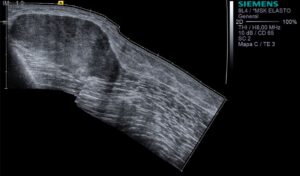

Ecografia de muslo derecho, modo B panorámico